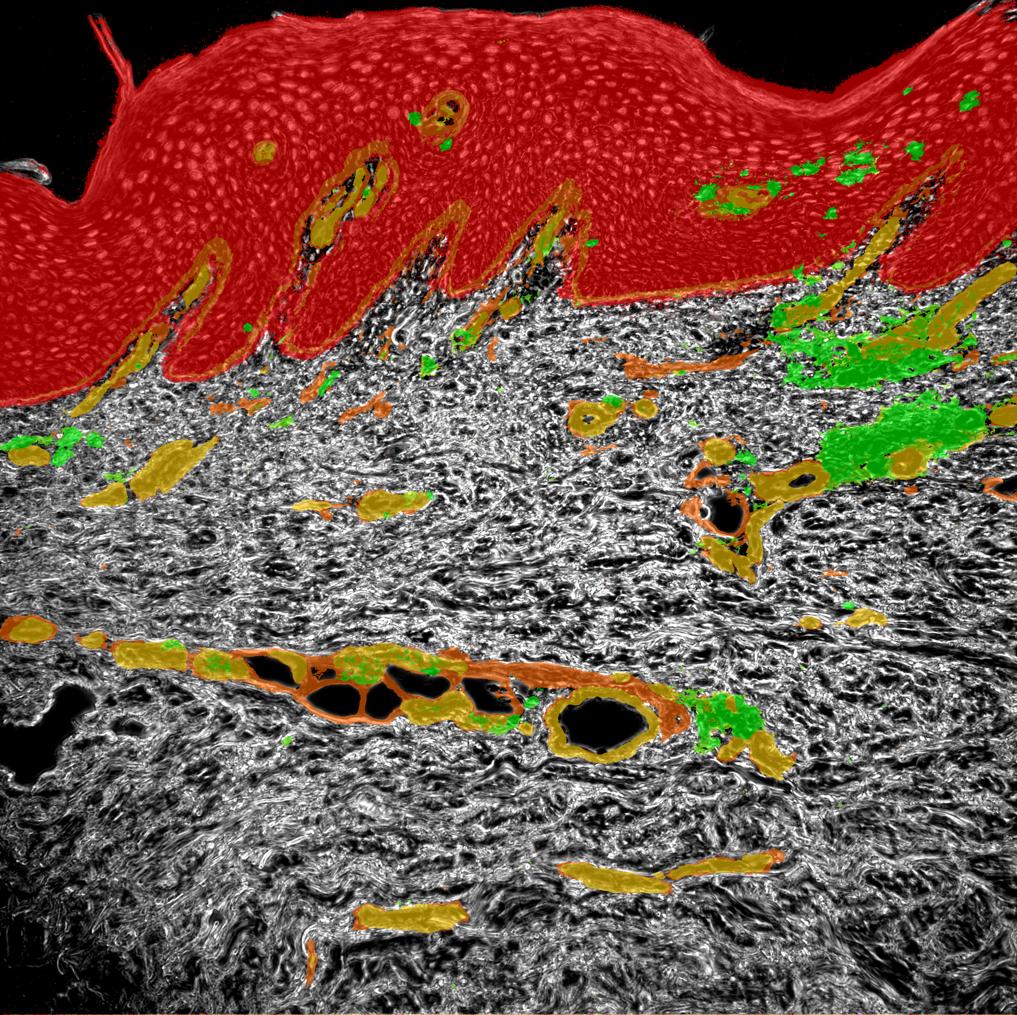

Phase contrast image

Keratinocytes

Collagen

Vessels

CD3 T cells

Psoriatic Skin

Human tissue section

Autoimmune loop